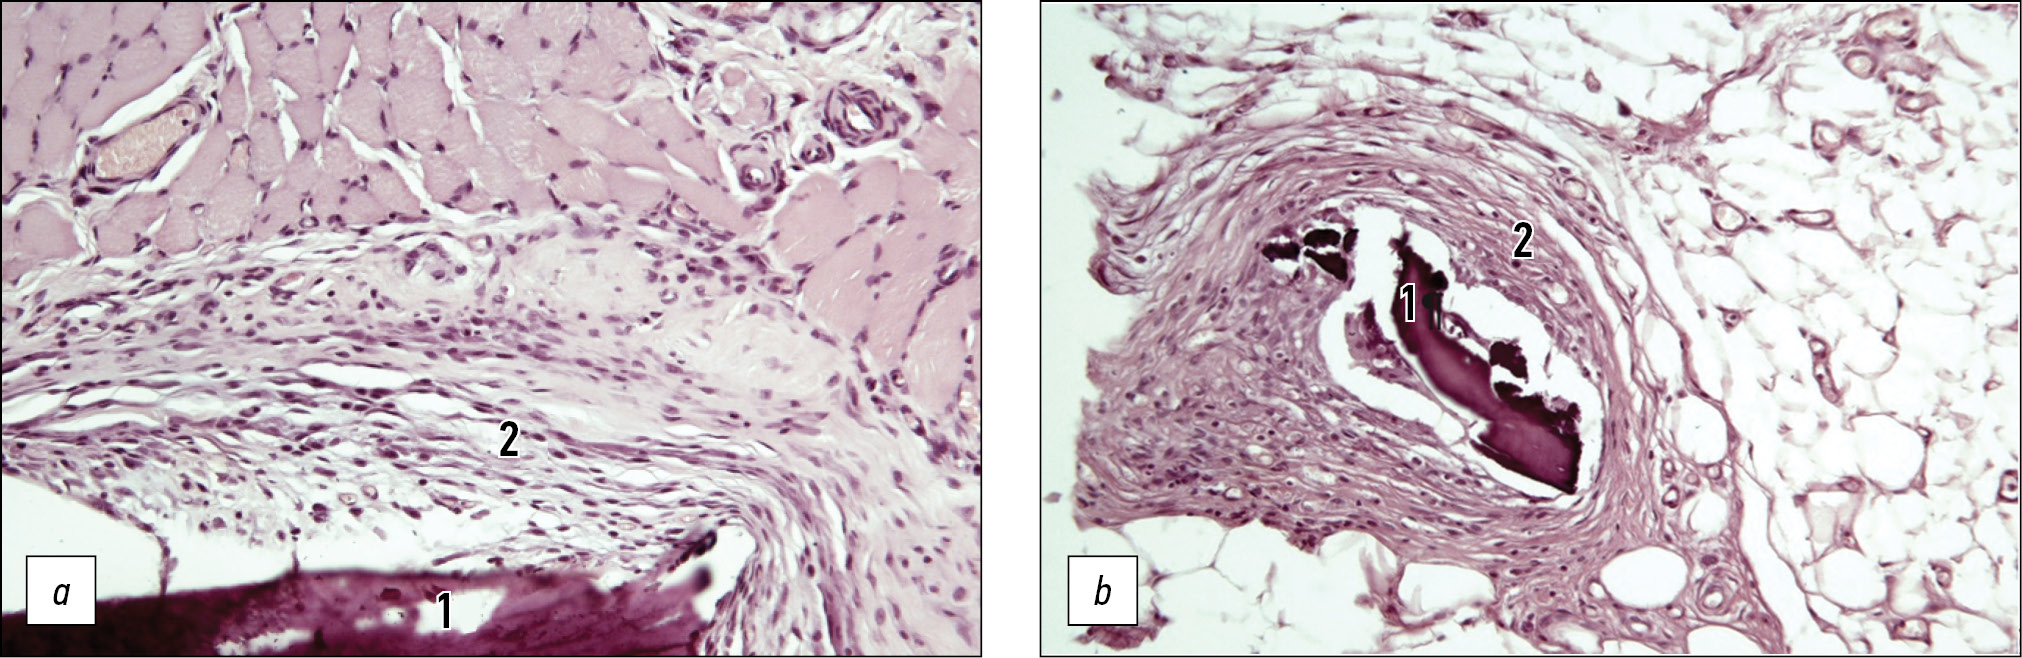

A morphological study showed that 14 days after subcutaneous implantation of the material, an immature connective tissue capsule had formed. The capsule had an inner layer adjacent to the implant and an outer layer bordering the fibers of the transverse striated muscles. The inner layer lacked neutrophilic leukocytes and contained loosely arranged histiocytes and a few unoriented fibroblasts. In contrast, the outer layer had fewer histiocytes and more fibroblasts, some of which formed bundles of oriented fibroblasts (Fig. 7a).

On day 30 after implantation, a connective tissue capsule had formed around the material. The capsule contained few cellular elements, predominantly oriented fibroblasts, and few histiocytes. Neutrophilic leukocytes and giant multinucleated foreign body cells were not detected (Fig. 7b). Bundles of collagen fibers were determined to have mostly developed in the outer layers of the formed connective tissue capsule, compared to the previous term of the study.

Fig. 7. Histological examination. Subcutaneous implantation. Standard light microscopy. Magnification ×200. Hematoxylin-eosin staining: a — on the 14th day (1 — implant fragment, 2 — forming connective tissue capsule, consisting of two layers); b — on day 30 (1 — implant fragment, 2 — maturing connective tissue capsule and forming bundles of collagen fibers).

On day 14, the implanted material underwent partial cellular resorption in the bone defect. Newly formed immature osteoid bone with a trabecular structure was detected in the most mature areas near the endosteal surface of the cortical plate, whereas no lamellar bone was observed. Additionally, cells of hematopoietic bone marrow were detected near the recipient margin. The newly formed bone near the central area of the defect appeared to be less mature than that in the marginal zone. Implant fragments were covered with loose connective tissue containing histiocytes, fibroblasts, and vessels of varying sizes. No neutrophilic leukocytes were detected. The cortical plate remained open, and an intermediate bone callus was observed (Fig. 8a).

By day 30 after implantation, the implant gradually resorbed, and relatively mature bone structures with a lamellar structure and osteons formed in the bone defect area. Furthermore, a cellular array of hematopoietic bone marrow was determined. At this point, the defect was almost closed because of the intermedial bone callus, and the implanted material was found in separate small fragments without osteocytes (Fig. 8b), and no signs of inflammatory reactions were found in any of the cases studied. No pronounced leukocytic or histiocytic reaction and no formation of giant multinucleated foreign body cells were detected.

Fig. 8. Histological examination. Bone implantation. Standard light microscopy. Magnification ×200. Hematoxylin-eosin staining: a — on the 14th day (1 — fragment of the implant, 2 — newly formed bone on the surface of the implant); b — on day 30 (1 — implant fragment, 2 — newly formed bone).